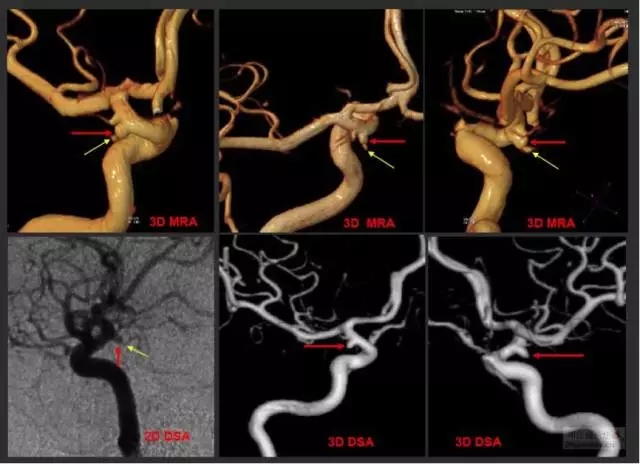

頭顱MRI(核磁共振成像):對于未出現(xiàn)動脈瘤破裂,僅以神經(jīng)壓迫癥狀前來就診或無癥狀體檢患者具有重要診斷作用,特別是大動脈瘤,頭顱核磁共振能夠有效發(fā)現(xiàn)并且初步診斷;而核磁共振血管造影(MRA)可以在發(fā)現(xiàn)顱內(nèi)可疑病變后用于確診是否存在腦動脈瘤,部分高場強核磁共振甚至能夠替代腦血管造影,作為一種無創(chuàng)的檢查方法收到越來越多的歡迎。

腦血管造影(DSA):診斷腦動脈瘤的金標(biāo)準(zhǔn),可動態(tài)和三維重建了解動脈瘤的位置、形態(tài)、數(shù)目、大小,以及與周圍組織結(jié)構(gòu)和周圍血管的關(guān)系,是決策下一步治療方案的主要依據(jù)。醫(yī)生最想知道的信息,包括腦動脈瘤的部位、形態(tài)、大小,都可以通過腦血管造影得到,并可以在明確腦動脈瘤的診斷后直接轉(zhuǎn)入對腦動脈瘤的治療。

CTA/MRA/DSA是確診腦動脈瘤的主要檢查手段